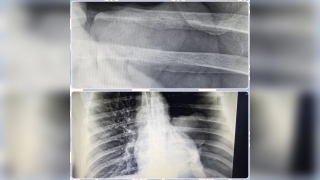

Пациента привили антирабической вакциной, он находится под наблюдением медиков.